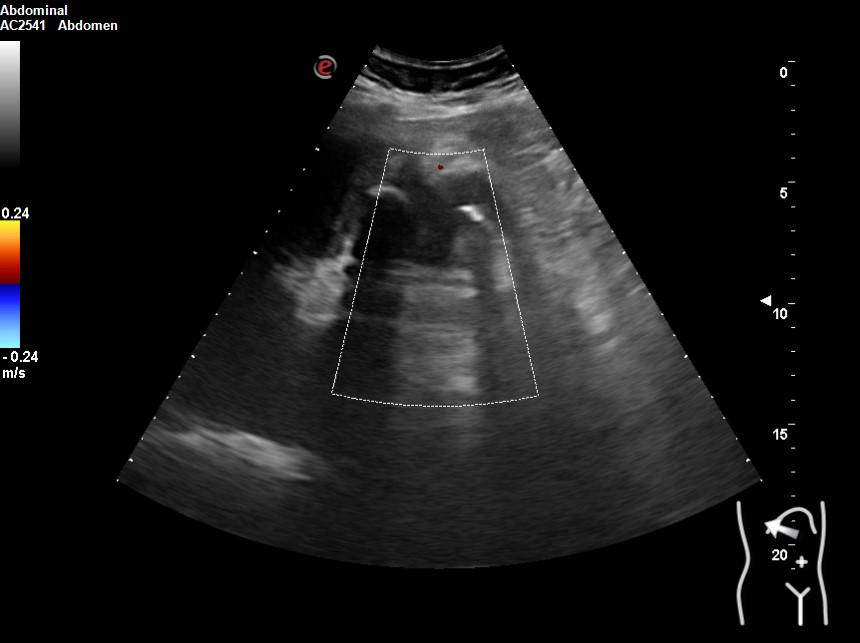

Hallazgos ecográficos

Vesícula biliar desestructurada, de paredes mal definidas con litiasis de 20 mm, que contacta con la pared de la segunda porción duodenal. Porta de tamaño normal. Vía biliar no dilatada.